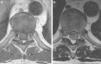

A dark pigmented intramedullary mass is very rarely encountered in daily practice, and poses a diagnostic challenge. Several entities have to be considered, including melanin-containing tumours (melanotic ependymoma and melanotic schwannoma) and melanocyte-containing tumours (melanocytoma, primary melanoma and melanoma metastases). The case is presented of a 47 year-old male with a pigmented intramedullary tumour located at T7-T8 level. Magnetic resonance images (MRI) revealed a tumour with hyperintensity on T1 and hypointensity on T2. The tumour was resected partially and treated with adjuvant radiotherapy. The diagnosis of primary intramedullary melanoma (PIM) was established based on histology and the absence of other lesions outside of the CNS. A literature review is presented on the other 26 PIM cases reported. PIM are extremely rare tumours, but are the most frequent cause of pigmented intramedullary tumour. Complete surgical resection is the treatment of choice whenever possible, followed by radiotherapy.